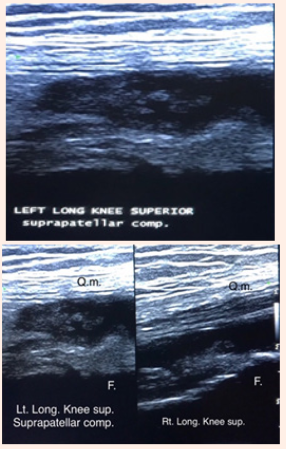

6. Ultrasound report of knee joint: Complete & real time exploration of Right and Left Knee.

7. Routine static and selective dynamic images were obtained in orthogonal plane. Normal gray scale sonographic findings of articular components.

8. Left long knee supra patellar compartment finding:

1. Well marketed homogeneous echogenic irregular thickened glandular appearance of synovial tissue.

2. Anechoic fluid appearance collection

No power Doppler signals intensity was shown.

The Right Knee sonography reveals minimum amount of fluid with homogeneous hypo echoic thickened synovium.

Figure 2 Left long knee superior suprapatellar compartment.

The sonographic homogeneous echogenic hyper atrophic nodullar appearance of the synovium was one of the important attracting attention followed by joint aspiration of haemorragic fluid of patient denies any trauma that enhanced the thinking of diagnosis of PVNS.